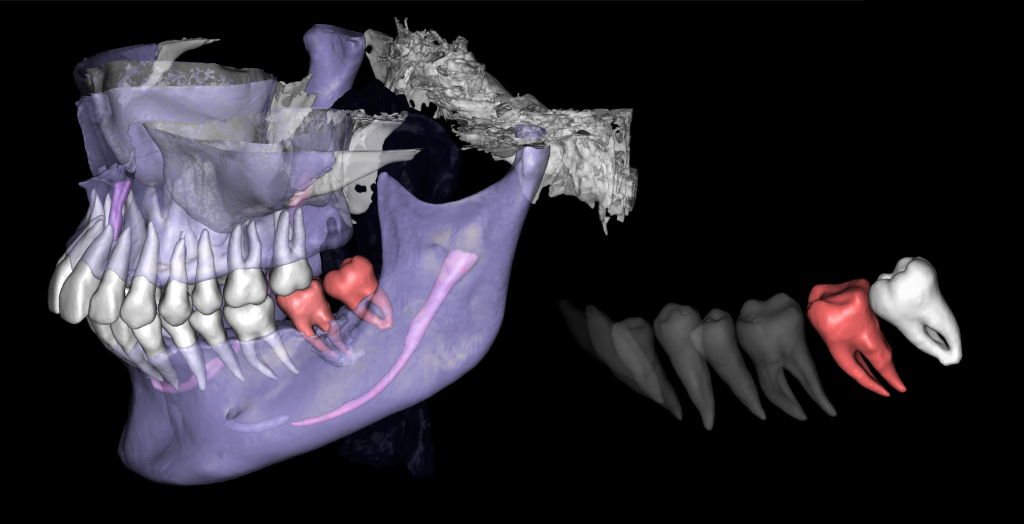

Solution: The automated process of segmentation and formation of 3D models from DICOM files allows extracting individual structures for subsequent 3D printing. The printed model of the third molar, taken from the “STL” module of Diagnocat, is used to prepare the socket for the transplanted tooth. The 3D reconstruction generated using Diagnocat displays the structure of the jaws and teeth and enables the visualization of tooth 37 (Universal 18) with periapical lesion around the roots. In this case, Diagnocat serves as a communication tool that helps convince the patient of the importance of timely implementation of the proposed treatment plan.